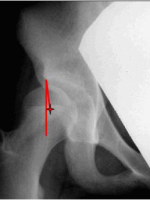

1) 先在X光片上测量需拉下股骨头旋转中心的距离,并在术中判断软组织松解后,是否可拉下此距离,此距离就是粗隆下截骨大约的高度(黄线)。